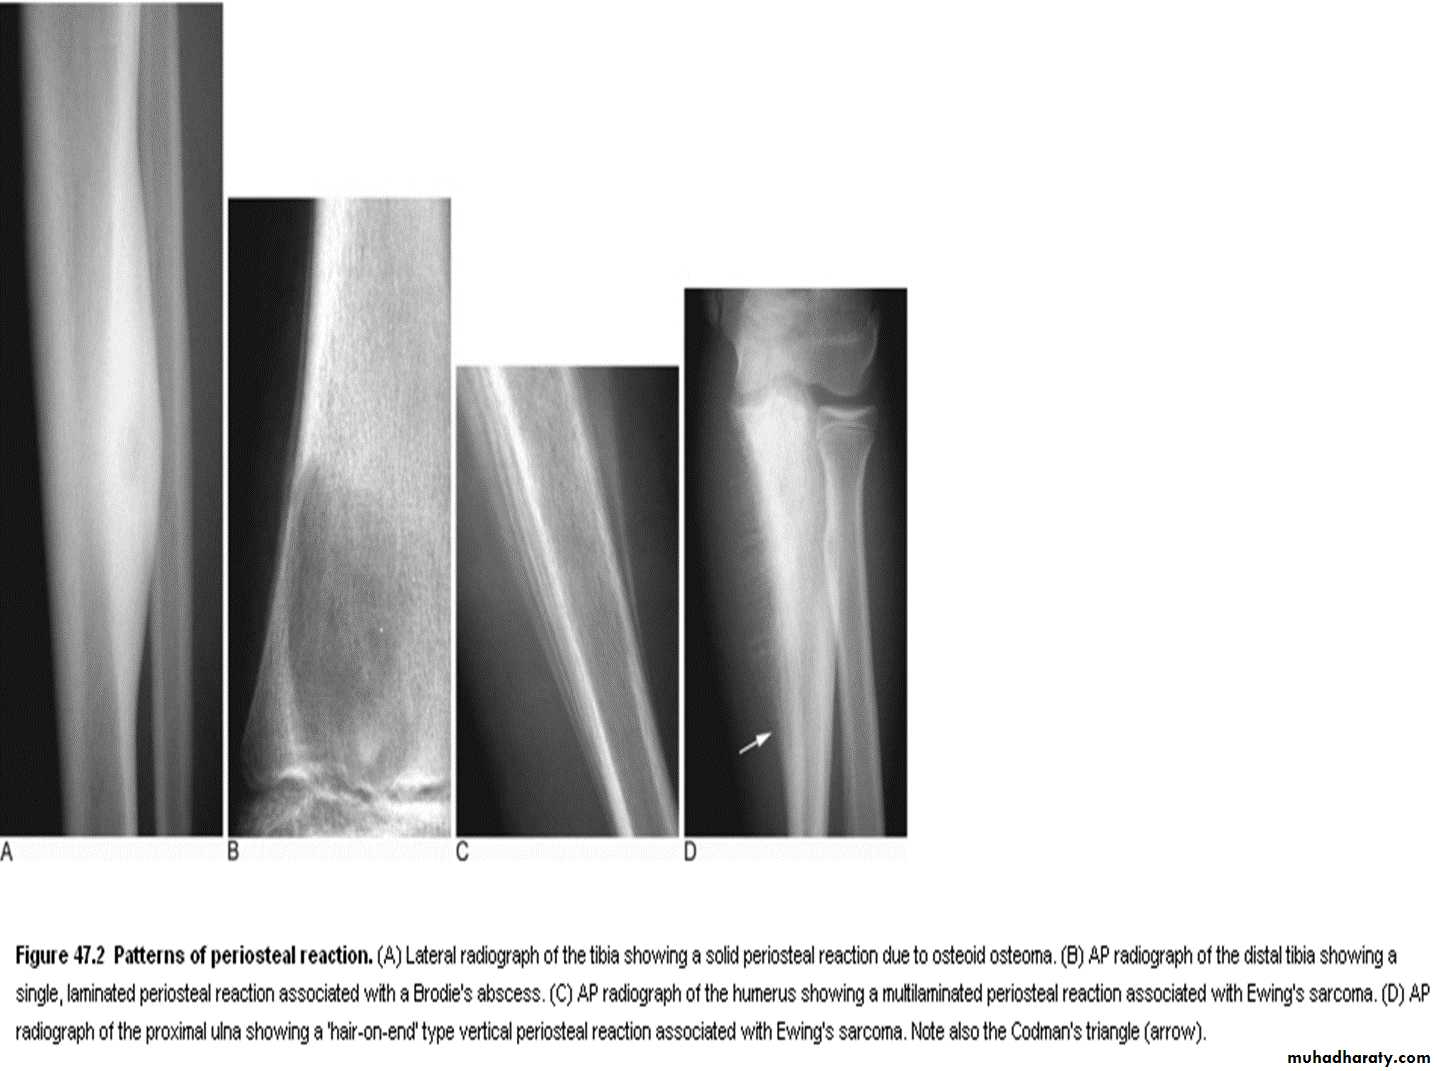

3- periosteal reaction :

Definition : new bone formation by the periosteum,

Normal periosteum is not visible.

The type of periosteal reaction does not correlate with specific diagnosis for e.g. Codman's triangle seen in osteosarcoma may be seen in other aggressive lesions.

4- Periosteal reaction:

in the absence of trauma periosteal reaction indicates aggressive lesion:

Osteomyelitis.

Malignant tumors: osteosarcoma, Ewing's sarcoma,

Metastasis (not uncommen) particularly Neuroblastoma